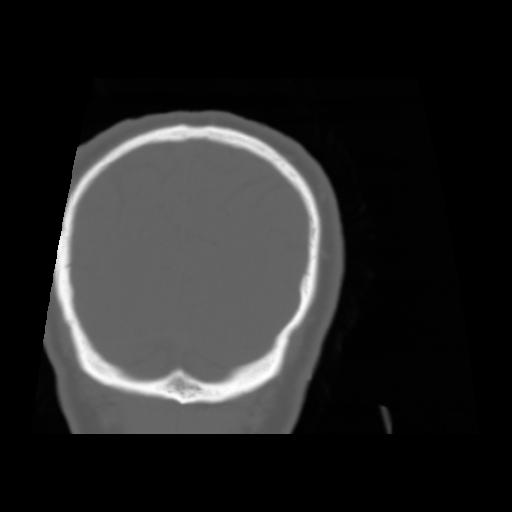

5 CEREBRO,,Coronal,3.000,CEREBRO,Coronal,